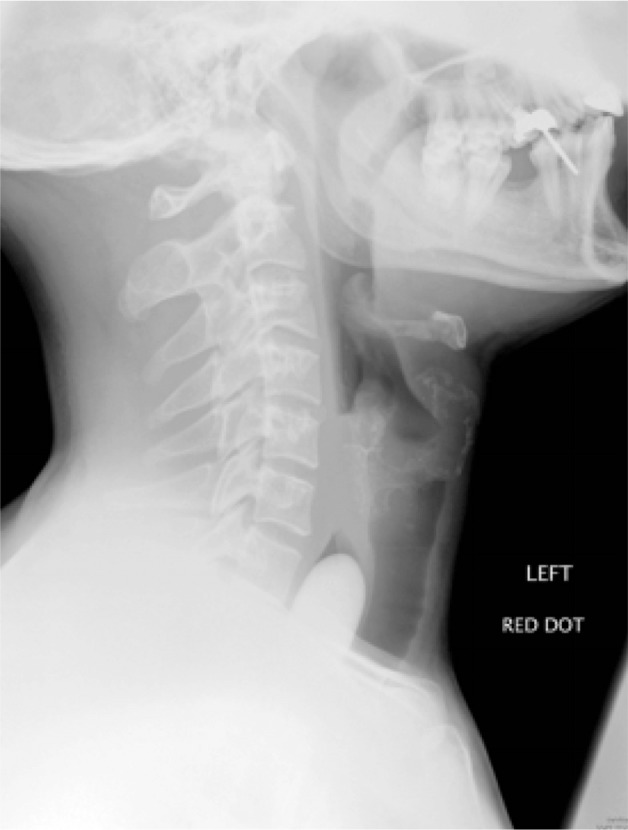

On examination, the patient was retching but maintaining his own airway. Examination of the oropharynx and chest was unremarkable, and there was no evidence of surgical emphysema. He declined flexible nasoendoscopy. A lateral soft tissue neck x-ray demonstrated a smooth, large opacity in the cervical oesophagus (Fig 1). A subsequent chest x-ray confirmed the position of the stone (Fig 2).

Figure 1.

Lateral soft tissue neck radiography showing radio-opaque foreign body extending from the upper level of the C7 vertebra. The foreign body was extending downwards into the thoracic inlet and the distal aspect of the foreign body was not visible.